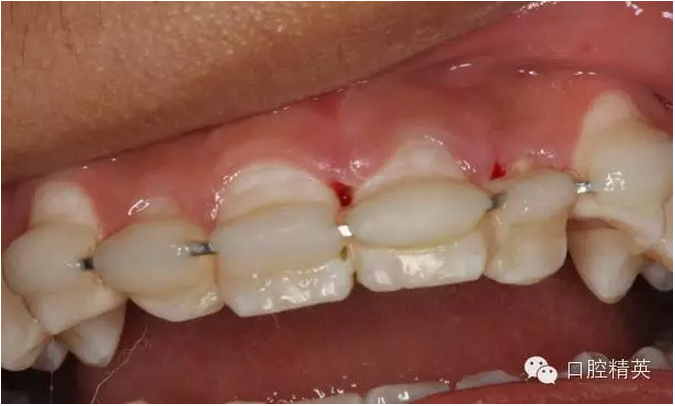

術(shù)后一個(gè)月的患者復(fù)查情況:

圖6.固定一個(gè)月后的唇側(cè)影像,牙齦及粘膜正常?;颊邿o(wú)任何自覺(jué)癥狀。

圖7.腭側(cè)口內(nèi)像,齦乳頭水腫消失

圖13.拋光完畢的牙面,齦乳頭色澤正常,無(wú)牙周袋。21不松動(dòng)

雖然21離體時(shí)間太長(zhǎng),預(yù)后欠佳,愈合方式為骨性粘連。容易出現(xiàn)牙根置換性吸收??梢允菚簳r(shí)性,能自然停止,也可以是進(jìn)行性的,直至牙齒脫落,這個(gè)過(guò)程但起碼維持?jǐn)?shù)年或數(shù)十年。這樣可以保持患側(cè)唇側(cè)豐滿(mǎn)度,又能維持患者到成人階段做永久修復(fù)。不失一種好方法。希望同道多提寶貴意見(jiàn)。共同提高?。?/p>